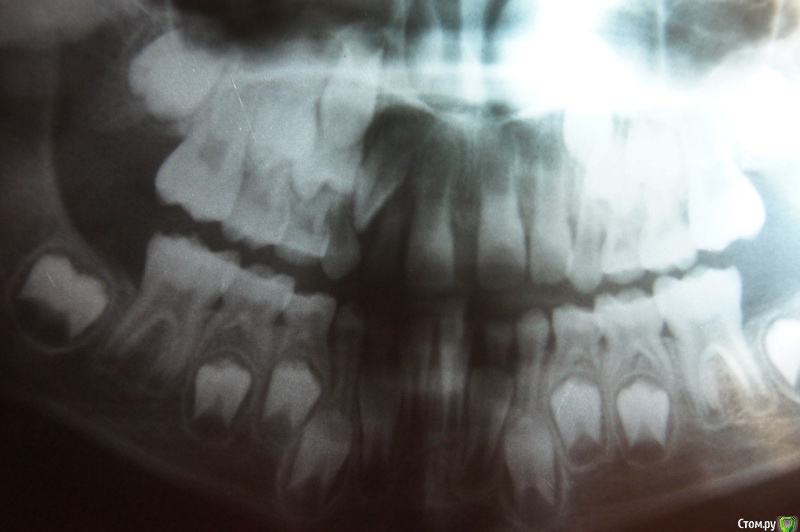

darida Опубликовано 2 февраля, 2016 Поделиться Опубликовано 2 февраля, 2016 (изменено) Ребёнок 8 лет (девочка). С рождения была массивная уздечка верхней губы (и "хвостик" из тканей десны между верхними передними резцами). Уздечку подрезали и подшили когда прорезались две постоянные единицы. Хвостик хирург не трогал, мотивируя тем, что когда зубы начнут сдвигаться (с помощью пластинки или брекетов - как решит ортодонт) - он рассосётся, так как мягкие ткани более податлитвы, чем рубцовые, которые образуется в случае его подрезания. Это было год назад.Через месяц после подрезания пошли к ортодонту. Ортодонт сказала приходить через год когда вылезут полностью постоянные двойки верхние, чтобы была возможность зацепить за них пластинку для устранения передней щели. На тот момент была только левая постоянная двойка, но кривая. Правая двойка по снимку тоже видно было, что вылезет кривой. Молочную правую двойку удалили вместе с подрезанием уздечки, так как не было даже намёка на шатание, а постоянная уже почти проклюнулась через десну над молочной.Двойки ортодонт сказала, что ровнять не будем пока не сменятся клыки.Несколько месяцев назад выпал сам правый молочный клык. Скорее всего его вытолкала эта постоянная двойка, так как очень-очень плотно стояла к нему, не было ни малейшей щели между ними (а вот между единицей и двойкой правыми - наоборот огромная щель, и многие (не врачи, естественно) даже принимают двойку за клык).В настоящее время побыли у другого ортодонта, которая предложила такой вариант: ориентировочно раз в год делать снимок, и когда будет видно, что постоянный клык уже продвигается вниз и скоро вылезет - поставить на передние верхние четыре зуба частичную брекет-систему (я уточняла на счет крепления - за шестёрки или как, но она сказала, что только именно на четыре зуба и всё) на месяца четыре ориентировочно, так как однокоренные зубы быстро сдвигаются и много времени не потребуется. А потом после становления резцов на место - установить со стороны языка "проволоку" до момента прорезывания клыков, чтобы зубы назад не разъехались.Пластинку она ставить категорически против, так как она наклоняет только коронку зуба и практически не воздействует на корень, то есть не подвигает зубы, а только наклоняет, а нам нужно именно передвигать (сдвигать) их.Прокомментируйте, пожалуйста, ситуацию и дайте советы и рекомендации.Если этих фото недостаточно, скажите какие ещё добавить.Снимок годичной давности, когда ещё был в наличии молочный правый клык. Изменено 2 февраля, 2016 пользователем darida Ссылка на комментарий